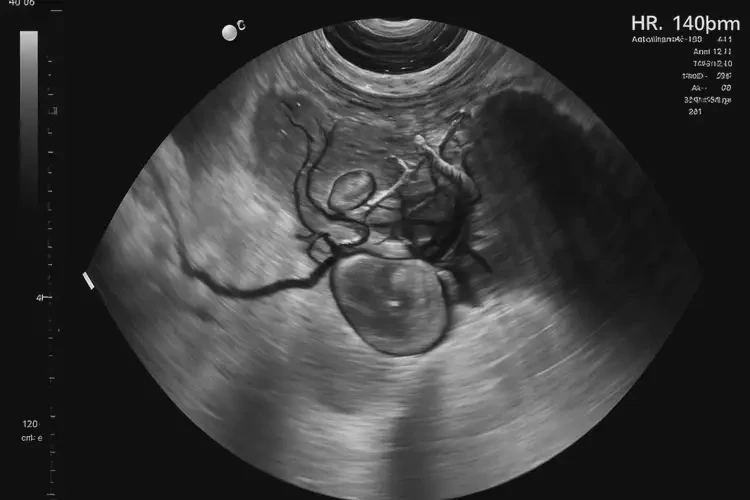

孕23周1天胎心80怎么回事(圖1)

孕23周1天胎心80怎么回事(圖2)

孕23周1天胎心80怎么回事(圖3) 孕23周1天胎心80怎么回事(圖4)